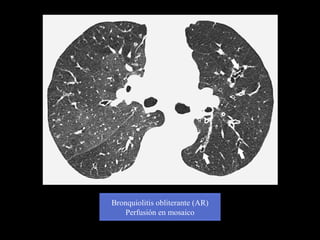

Bronquiolitis obliterante (AR)

Perfusión en mosaico